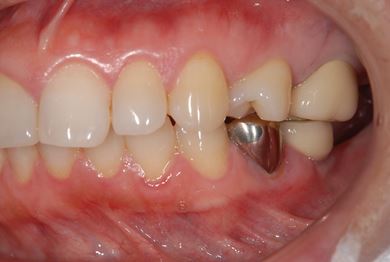

インプラントの症例写真 IMPLANT

インプラント治療+セラミック治療

| 主訴 | 前歯や、下の奥など、何本か気になる歯がある。 | ||||||||||||||||||||||||||||||||

| 治療方針 | インプラント治療により、機能的・審美的回復を行う。 | ||||||||||||||||||||||||||||||||

| 治療内容 | インプラント2本、メタルボンドセラミッククラウン4本、ジルコニアフレームオールセラミッククラウン1本(オールセラミック用土台1本) | ||||||||||||||||||||||||||||||||